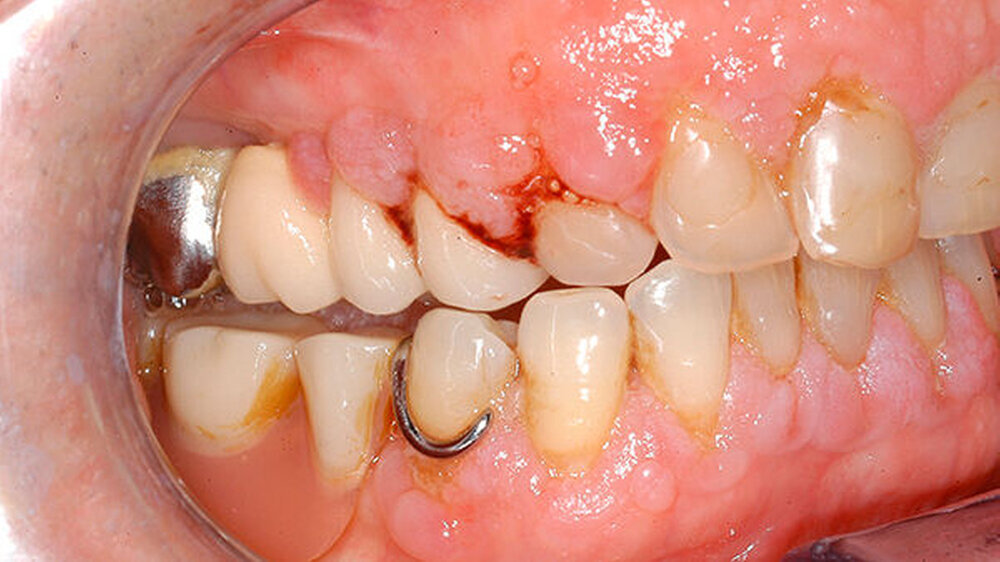

Bei der intraoralen Inspektion zeigte sich eine deutlich hyperplastische Gingiva mit Blutung auf Sondieren (BOP) (Abbildung 1). Da der Patientin die Handhabung einer Zahnbürste schwerfällt, zeigten sich auch deutliche Plaqueanlagerungen.

Aufgrund der schmerzhaften Gingivitis hatte die Patientin zudem Probleme mit der Nahrungsaufnahme. In der Panoramaschichtaufnahme (Abbildung 2) zeigt sich neben einem impaktierten Eckzahn ein Furkationsbefall der Molaren mit Konkrementen sowie ein altersentsprechender, generalisierter horizontaler Knochenabbau. Dennoch erschien uns das Volumen der Gingiva nach bereits erfolgter geschlossener Parodontaltherapie ungewöhnlich.